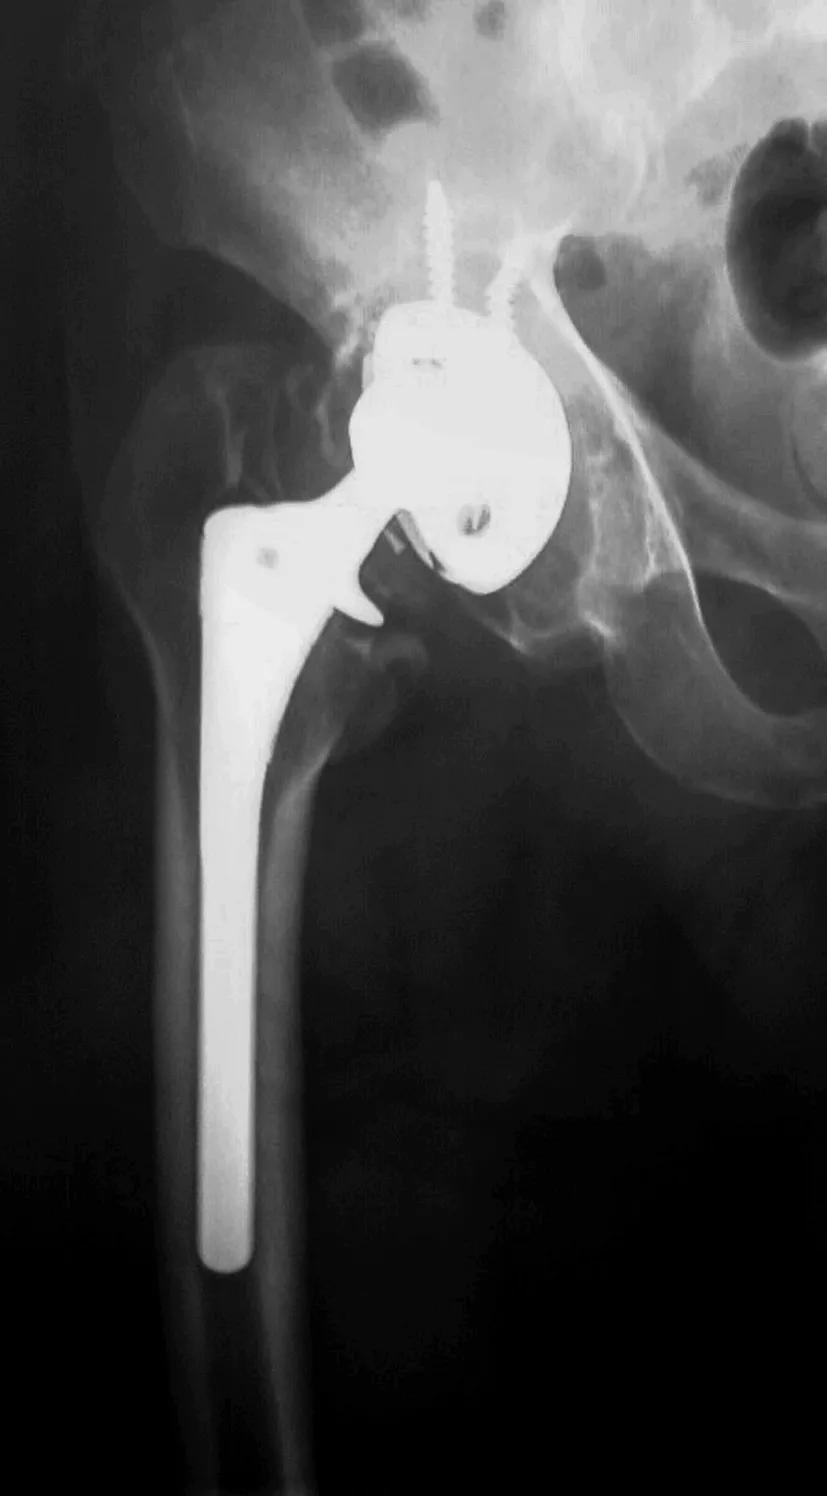

人工髋关节翻修术的模板测量步骤与初次置换相同,首先测量髋臼侧,标记确定旋转中心后,然后再围绕旋转中心进行股骨侧模板测量。模板测量时应注意以骨缺损分型为指导选择合适类型的假体,其大小可用模板在X线片上重叠测量。以髋臼侧翻修最常用的多孔涂层的半球形髋臼杯为例,第一步将模板放置到X线片上,使髋臼杯获得最大骨性覆盖,若宿主骨与臼杯接触50%~60%,根据具体骨缺损情况可以选用骨小梁金属臼杯、髋臼支架结合结构性植骨、Cup-Cage结构、定制三翼臼杯等(详见第四章)。

股骨柄的长度一般应越过任何股骨缺损(bypass defects),并超过该处股骨髓腔直径2~3倍的长度。对于广泛涂层股骨柄而言,其宽度(直径)应能满足与远端完整皮质骨的接触区域大于5cm,以提供充分的初始稳定。若担心强度不够,应考虑准备异体骨板,术中支撑性植骨(strut graft)以增强股骨强度,降低骨缺损部位的骨折风险。若所选假体长度大于15cm时,必须在侧位片上评估假体与股骨前弓匹配程度,以确定是否用一个弯柄而避免造成股骨骨折或穿孔。此外还应注意所选假体应该有适宜的颈长及偏心距,以尽量纠正双下肢不等长及优化外展肌功能,防止碰撞。(旋转中心的确定应根据下肢计划延长多长,旋转中心则应相应垂直提高多少来定;偏心距应在内旋15°的正位片上来确定,以抵消股骨前倾)。